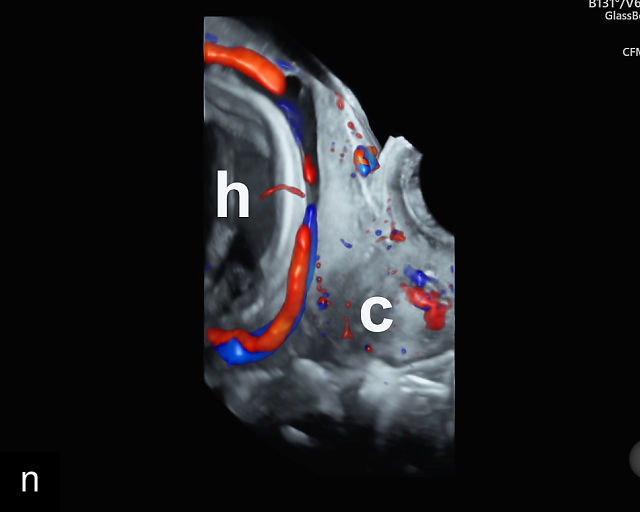

Vasa previa

Vasa previa refers to unprotected fetal vessels running through the membranes over the cervix.30,50,252,253 These vessels often rupture when the membranes rupture during labor or in late pregnancy, resulting in fetal hemorrhage and often exsanguination.252 As a result, this condition is associated with high perinatal mortality.35,252 A large study found a 56% perinatal mortality when vasa previa was not diagnosed prenatally.35 Prenatal diagnosis with ultrasound and cesarean delivery before labor or rupture of the membranes prevents this high perinatal mortality.254,255,256 Risk factors for vasa previa include second-trimester placenta previa or low-lying placenta, velamentous cord insertion, pregnancy resulting from in-vitro fertilization, multifetal gestation and placenta with accessory lobe.30,36,50,257,258,259,260,261

There are three types of vasa previa.30,262 In Type 1, the cord inserts into the membranes rather than the placenta. Unprotected vessels then traverse the membranes over the cervix to insert into the placenta (Figure 21a; Video 12). In Type 2, unprotected vessels running through the membranes over the cervix connect the main placental lobe with an accessory lobe (Figure 21b).263 In Type 3, there is generally a normal placental cord insertion, and unprotected vessels exit one placental edge, run through the membranes over the cervix and then boomerang to insert into the placental edge at another site (Figure 21c).25,28,29,264 Regardless of the type, all these expose the fetus to the same risks.

21